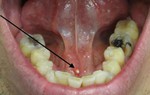

Bệnh tưa miệng (Ảnh: Internet)

Mụn rộp miệng do herpes (Ảnh: Internet)

Loét miệng có thể gây loét cả lưỡi (Ảnh: Internet)